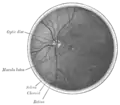

Cross-section of human eye, with choroid labeled at top.